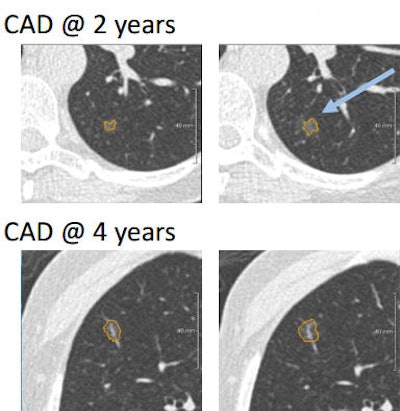

CIRRUS Lung Screening semiautomatic CAD software (Nijmegen, the Netherlands) was used for detection and characterization of pulmonary nodules on baseline, two-year, and four-year low-dose CT studies.

Visual reading and CAD analysis were performed four years apart, and the investigators measured total diameter and the diameter of the solid component of the nodule. CIRRUS also recorded the volume of the solid component, total mass, and mass of the solid component of the nodule.

Persistent subsolid nodules were detected by CAD after baseline in almost 50% of cases (11/23), Silva said.

"It is also noteworthy that all [eight] subsolid nodules growing into a tumor were detected by CAD," he said.

"In conclusion, CAD detected a large number of relatively small subsolid nodules in subjects that were overlooked by visual detection," Silva said. CAD revealed exceptionally higher sensitivity for part-solid nodules in particular. Some nodules were not detected by CAD in the initial screening round, but if they were persistent, they were detected at subsequent CT screening rounds.